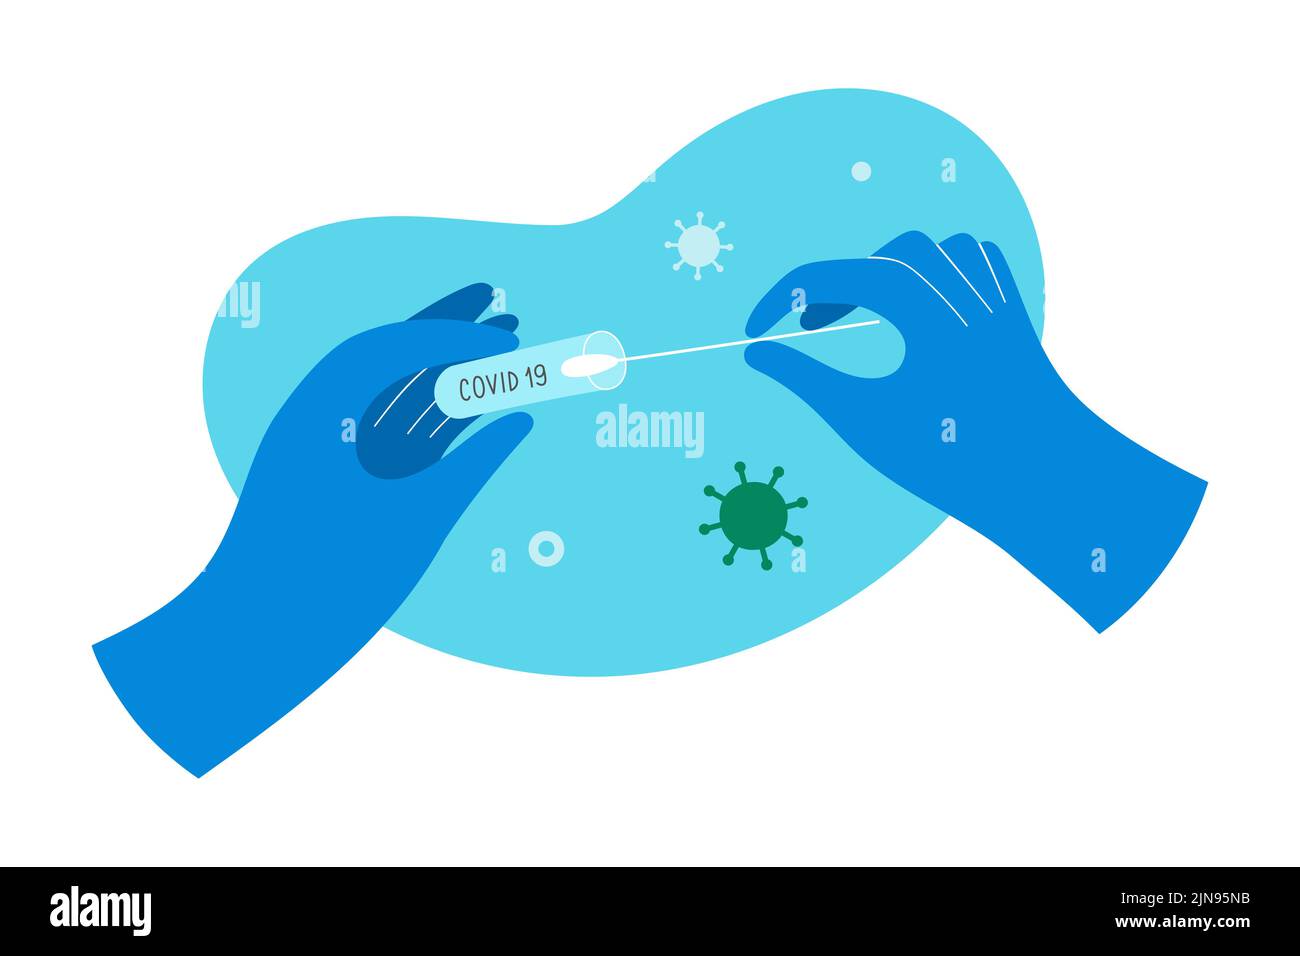

RF2BY648K–Test Covid, médecin recueille le mucus nasal par échantillon d'écouvillon pour l'infection à Covid-19, patient testé, analyse de laboratoire, examen médical, vecteur de dessin animé plat

RF2JN95NB–Tenant un tube à essai rapide covid dans les mains avec des gants, un médecin tenant un kit de test pour le coronavirus, un écouvillon en coton nasal, une illustration vectorielle